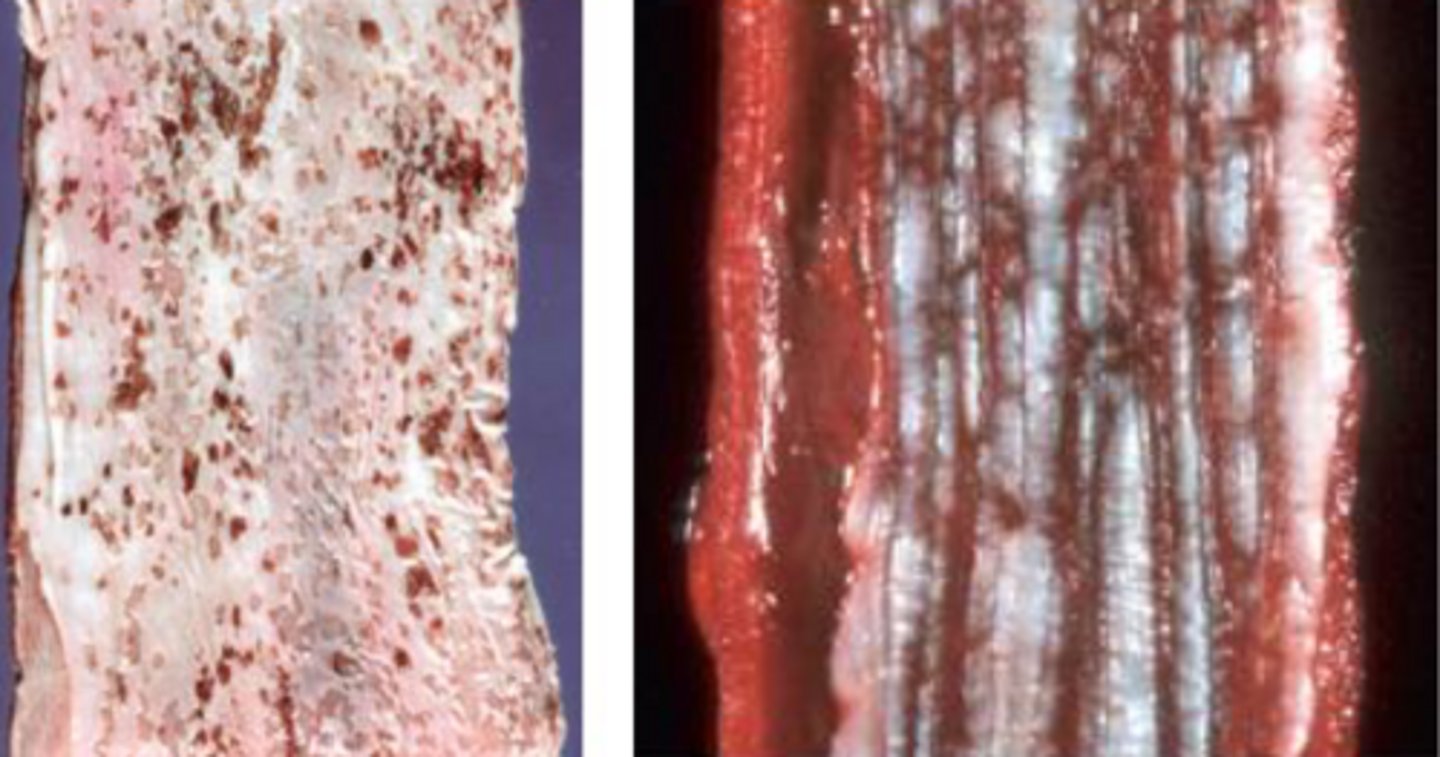

Esophageal stricture

-chronic inflammation/ ulceration leading to fibrosis

Identify the pathology?